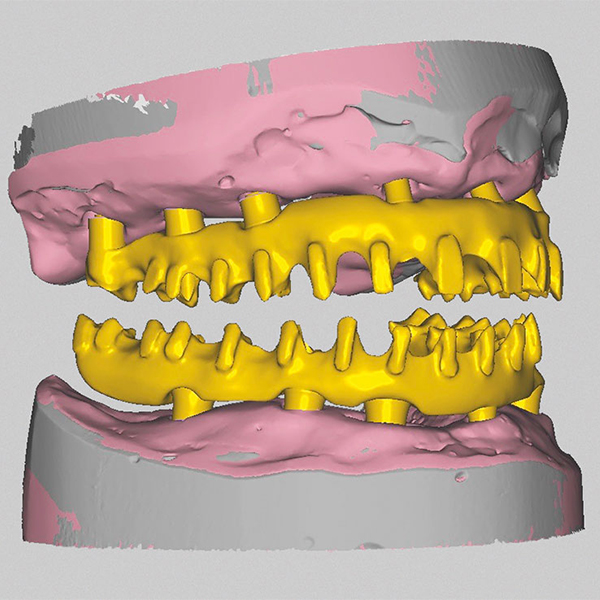

Après la mise en moufle et l'ébouillantage, les dents ont été repositionnées, conditionnées et des caractérisations blanchâtres, pourpres, orange clair, bleues et roses ont d'abord été réalisées au niveau du le bouclier labial. La base a ensuite été incrustée de résines pour prothèses de couleurs orange-rouge, rouge foncé, rouge clair, rose et rose foncé, et tous les polymères à chaud ont été pressés en une seule fois. Après le stockage sous pression, les prothèses finies ont été démouflées, finies et polies. La stratification anatomique tridimensionnelle de VITAPAN EXCELL en masse d'émail, de collet et de dentine avait un aspect absolument naturel dans l'anatomie muco-gingivale reproduite de la base prothétique. Le patient a pu s'habituer rapidement à sa nouvelle prothèse, notamment grâce à l'effet esthétique réussi. Après une courte phase d'adaptation et des corrections minimes dans l'environnement biodynamique, il s'est très bien débrouillé avec sa première restauration prothétique amovible complète et en était pleinement satisfait.